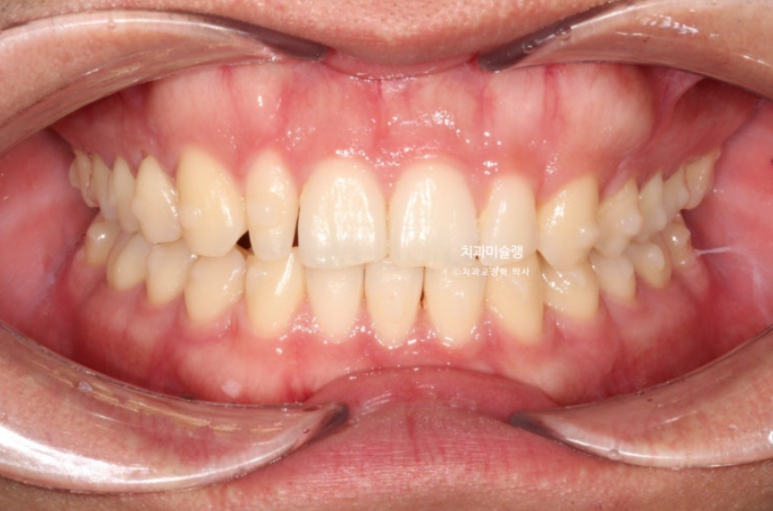

왜소치 덧니쪽으로 쏠려있던 앞니 중심선이 비로소 중간으로 맞춰졌습니다.

24.03~25.11

옥니의 개선으로 미소가 환해졌습니다.

입매변화는 없이 잘 유지가 되었고 위 앞니 각도의 옥니 개선이 눈에 띕니다.